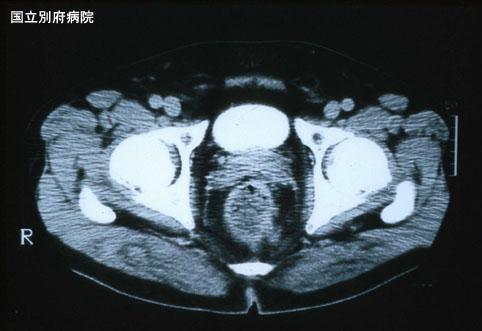

폐전이를 동반한 직장의 악성흑색종(증례제시:국립 벳부병원)

[Image-ID:3127]

질환(병리주체)의 분류

악성흑색종/

부위(장기별)

대장/직장

검사방법

CT

종양의 심달도

ss(a1)